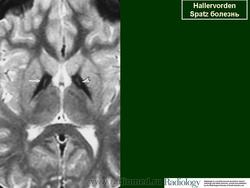

ГМ. Галлервордена - Шпатца болезнь. +

Галлервордена - Шпатца болезнь

Болезнь Галлервордена - Шпатца - наследственное заболевание экстрапирамидной системы, связанная с нарушением обмена железа и липидов и повреждением бледного шара и черной субстанции. Тип наследования аутосомно-рецессивный. При патоморфологическом исследовании характерным признаком является гиперпигментация бледного шара и черной субстанции. Обнаруживается пигментация коры полушарий большого мозга и таламуса. Пигмент находится внутри невронов и глиальных клеток, расположенных около сосудов; содержит железо (вместе с тем каких-либо нарушений обмена железа в организме не обнаружено). Наблюдаются утолщение и фрагментация аксонцилиндров в пораженных областях. Постепенно наступает дегенерация невронов коры полушарий большого мозга и мозжечка. Характеризуются нарастающей экстрапирамидной ригидностью, гиперкинезами (атетоз, торсионная дистония), затем развивается акинетико-ригидный синдром, пирамидная микросимптоматика, снижение интеллекта. Течение медленно прогрессирующее на протяжении 10 - 20 лет.

"Глаз тигра"-наглядно и красиво.

Вы правы. Выставил еще более нагладные исллюстрации.